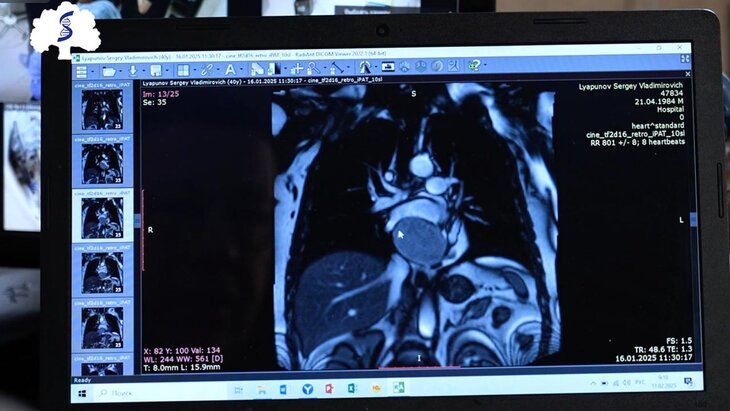

Московские врачи удалили пациенту опухоль размером с яблоко в сердце

Кардиохирурги Сеченовского Университета удалили пациенту опухоль в сердце, размер которой был сопоставим с яблоком, сообщила пресс-служба организации.

Около полугода назад мужчина получил травму грудной клетки. В ходе дальнейшего обследования по месту жительства было установлено, что за левым предсердием пациента возникло объемное новообразование.

По итогам нескольких консультаций медики пришли к заключению о необходимости удаления опухоли. В частности, мужчине рекомендовали провести операцию на сердце с традиционным доступом, то есть через распил грудины.

Тем не менее пациент хотел найти клинику, где опухоль смогли бы удалить менее травматичным способом. В результате он обратился в Клинику сердечно-сосудистой хирургии Сеченовского Университета, сотрудники которой обладают значительным опытом в области мини-инвазивных оперативных вмешательств на сердце.

Врачи успешно удалили новообразование, которое оказалось доброкачественным. К настоящему моменту пациент полностью здоров и теперь ему лишь предстоит проходить периодические обследования.